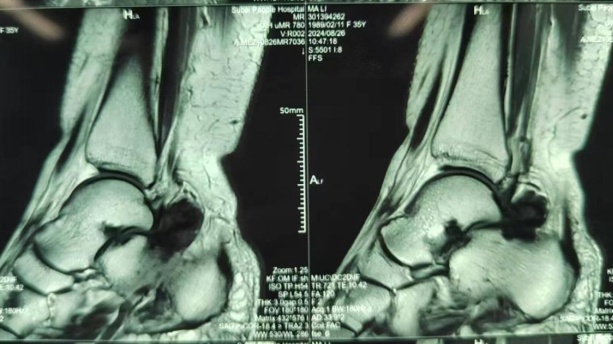

最近马女士觉得疼痛感愈发加重,来到市六医院金山分院诊治,接诊医生在为马女士做了MRI检查后发现,马女士的踝关节里居然有绒毛样的结节状阴影,结合问诊及检查报告等,考虑为左踝关节色素沉着绒毛结节性滑膜炎。

马女士的MRI检查

踝关节MRI上表现为踝关节内局灶性、结节样或弥漫性增生的滑膜,一般无钙化,可呈均匀高密度影,也可有关节囊积液。